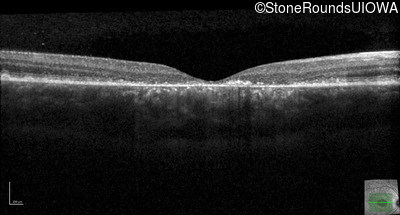

Optical Coherence Tomography - Right - 20/125 sc

Exemplar / OCT Stack

OCT Stack

Optical Coherence Tomography - Left - 20/125 sc